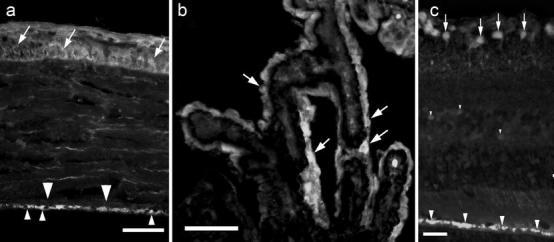

Cystatin C administered intravitreally in vivo is taken up into cells of the corneal endothelium and epithelium, the epithelial cells lining the ciliary processes, and into cells in the neuroretina (mostly ganglion cells) and the retinal pigment epithelium. The uptake is demonstrable also in vitro and was, in the neuroretina, found to be a high-affinity system, inhibited by cooling the specimens or by adding the microfilament polymerization inhibitor, cytochalasin D, to the medium.